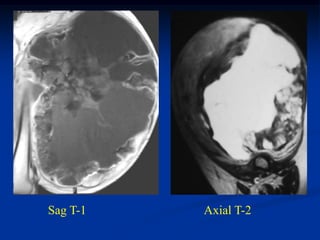

Case #1186

51 year male with

intramuscular lipoma

posterior compartment

thigh

Axial T-1 MRI

Case #1186 51 yearmale with intramuscular lipoma posterior compartment thigh

• 58.

• 59.